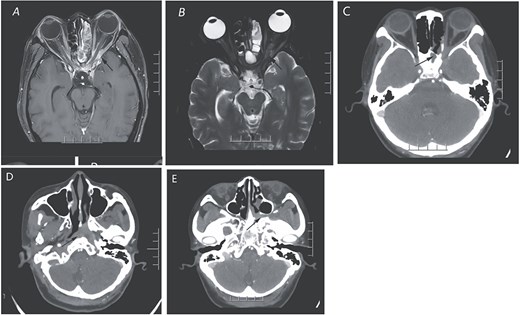

Magnetic resonance imaging (MRI) revealed a mass in the left orbital apex and spheno-ethmoidal recess, involving the adjacent optic nerve, ophthalmic artery, and extraocular muscles (Fig. 1A and B). CT scan demonstrated opacification of the sphenoid and posterior ethmoid sinuses with bony erosion, a mass extending into the orbital apex, pterygopalatine fossa, and nasopharynx (Fig. 1C–E). These findings were suggestive of an inflammatory lesion, but neoplastic disease could not be excluded.

The orbital enhanced MRI scan (A and B) illustrates the presence of an enhancing inflammatory phlegmon that extends from the left sphenoid sinus through the orbital apex and involves the extraocular muscles of the left orbit. Additionally, there is an abnormal swelling of the left optic nerve. In panel C, the CT scan of the paranasal sinuses in the coronal view reveals a mass in the sphenoid sinus and posterior ethmoid sinus, along with bone destruction and a suspicious soft tissue mass affecting the left orbital apex. Panels D and E display the extension of the mass into the left pterygopalatine fossa and the presence of a suspicious soft tissue mass in the left nasopharynx, indicated by arrows.